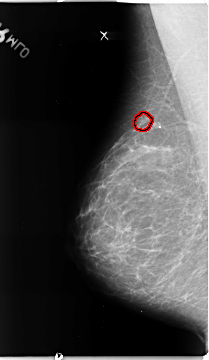

B_3136_1.RIGHT_MLO

FILE: B_3136_1.RIGHT_MLO.OVERLAY

TOTAL_ABNORMALITIES 1

ABNORMALITY 1

LESION_TYPE CALCIFICATION TYPE PLEOMORPHIC DISTRIBUTION CLUSTERED

ASSESSMENT 4

SUBTLETY 4

PATHOLOGY MALIGNANT

TOTAL_OUTLINES 1

BOUNDARY